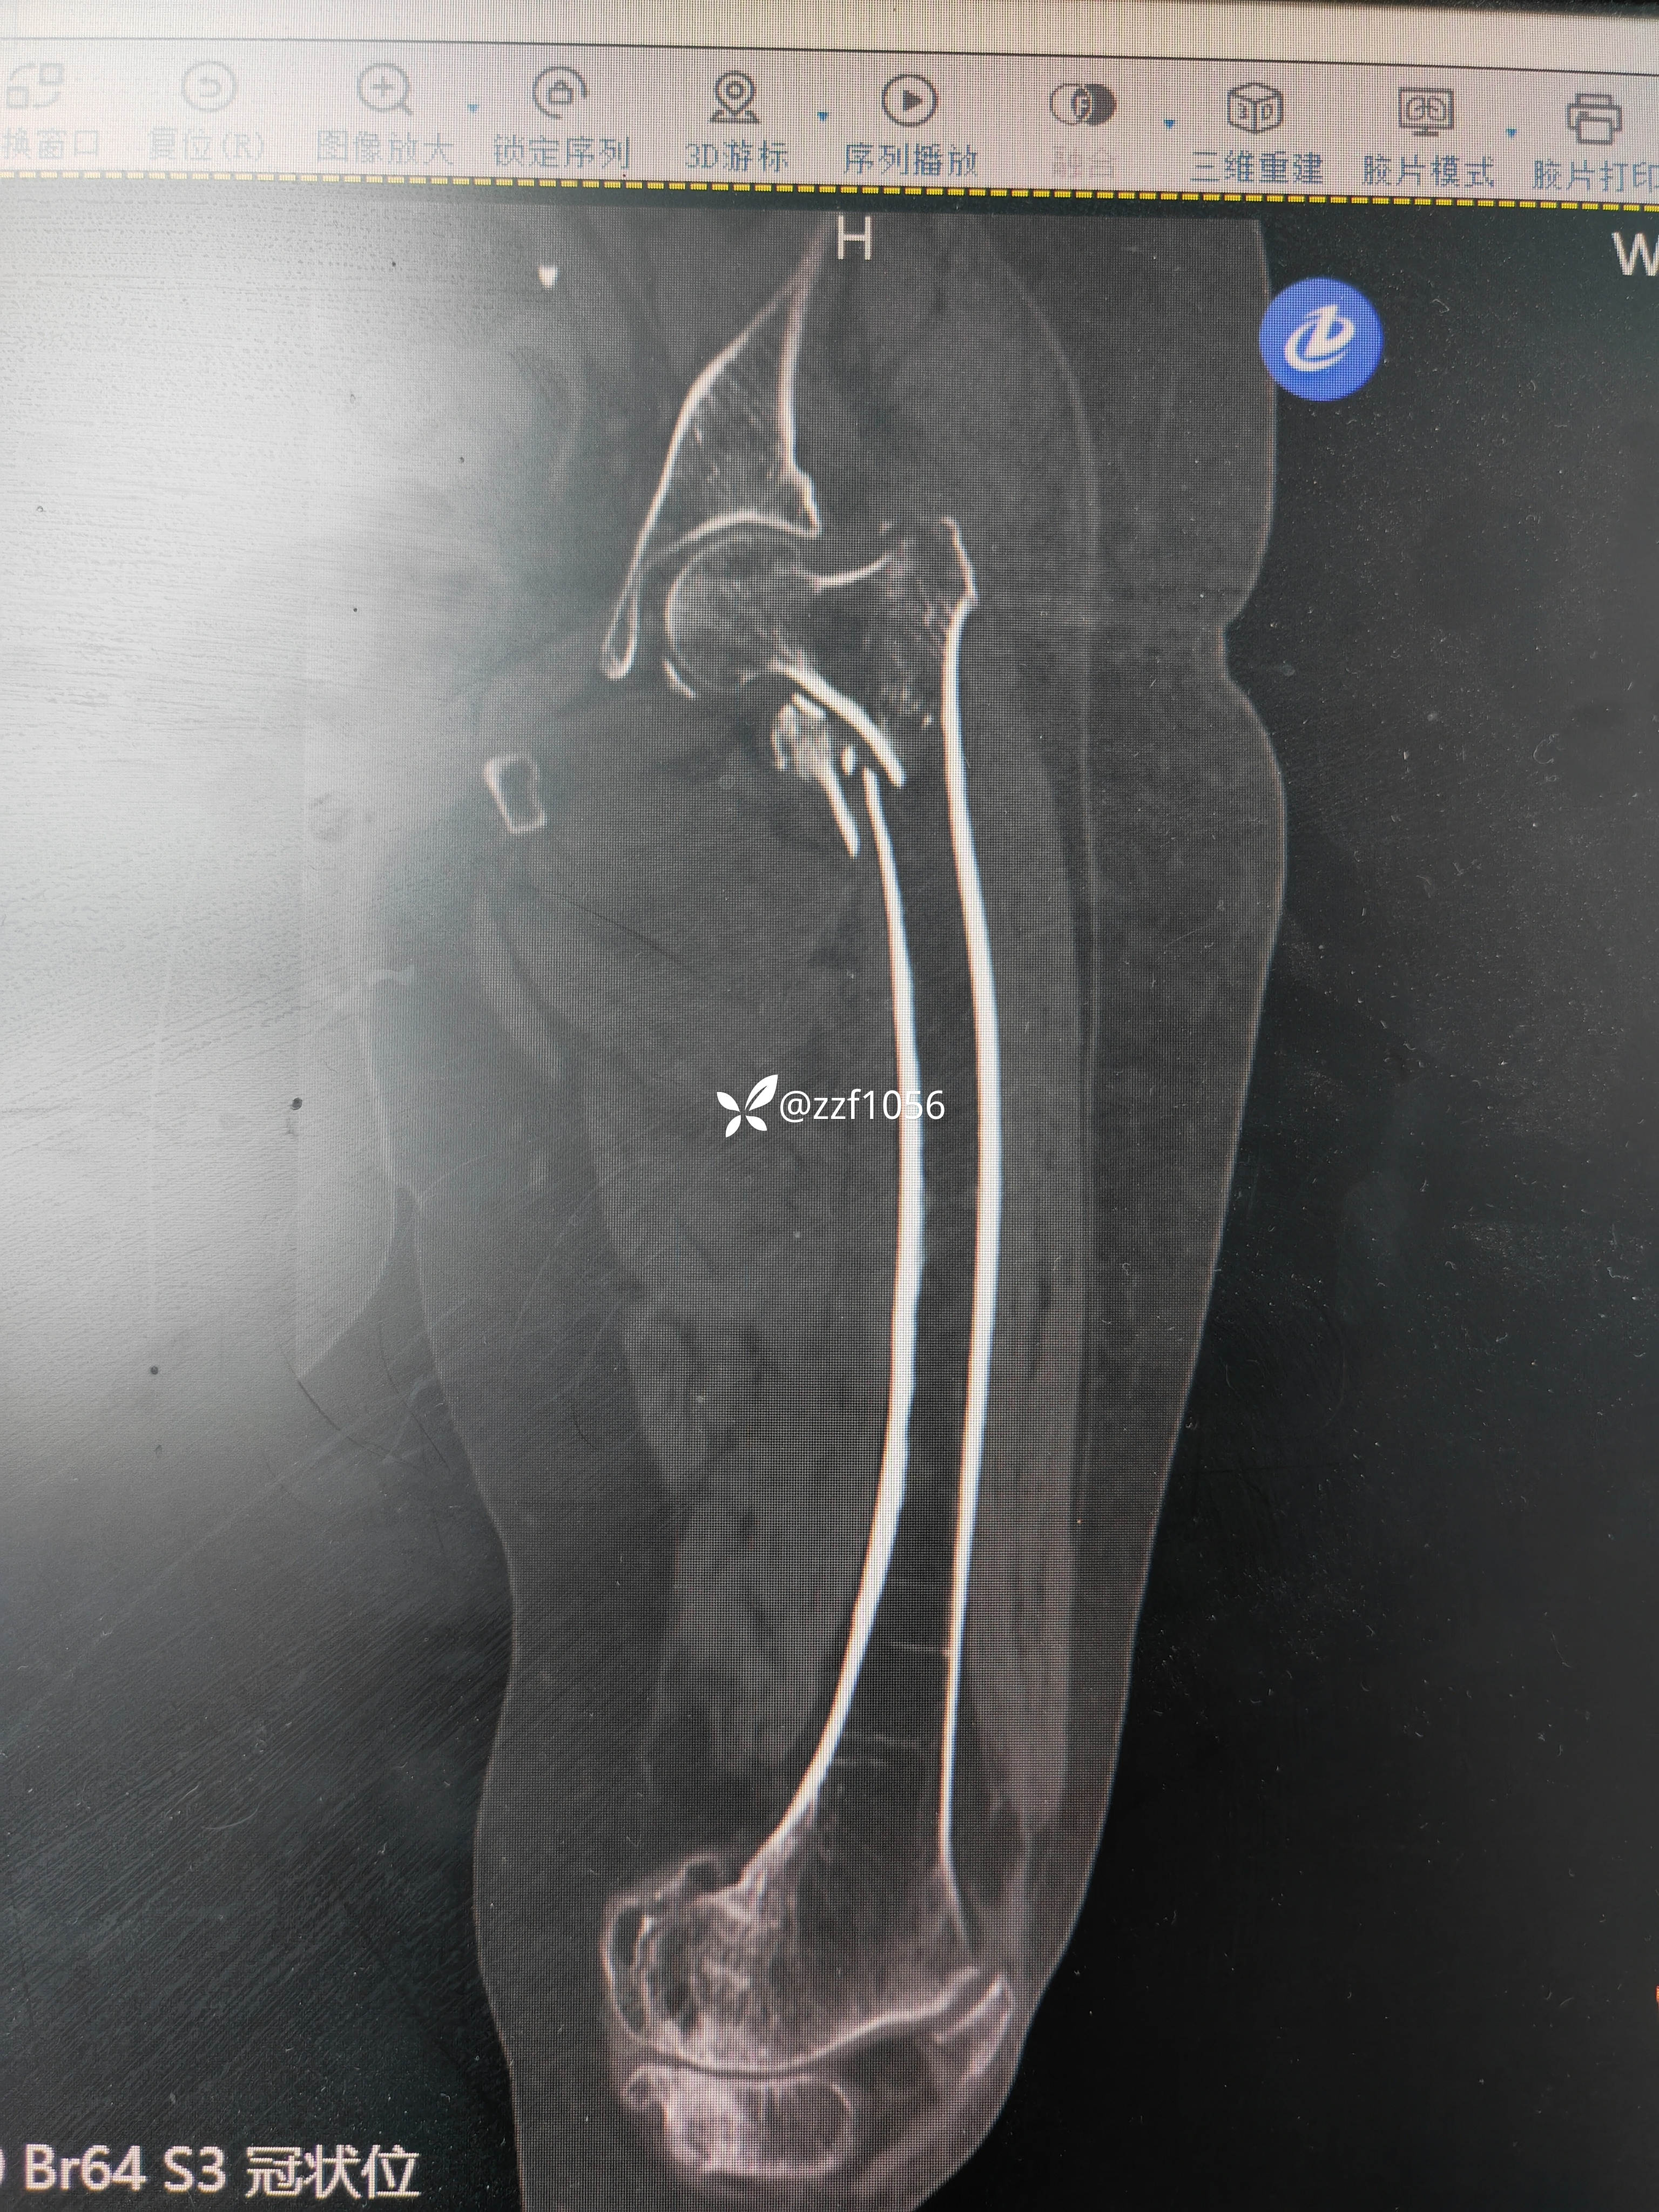

术中去除内固定顺利,使用瓦格纳柄,术中出现插曲,出血量多和干部骨折,多处捆扎,全髋改半髋下台,😰虐心,懂得都懂

行走三个月康复良好,奈何再次摔伤,导致左侧转子间再骨折,A2.3型